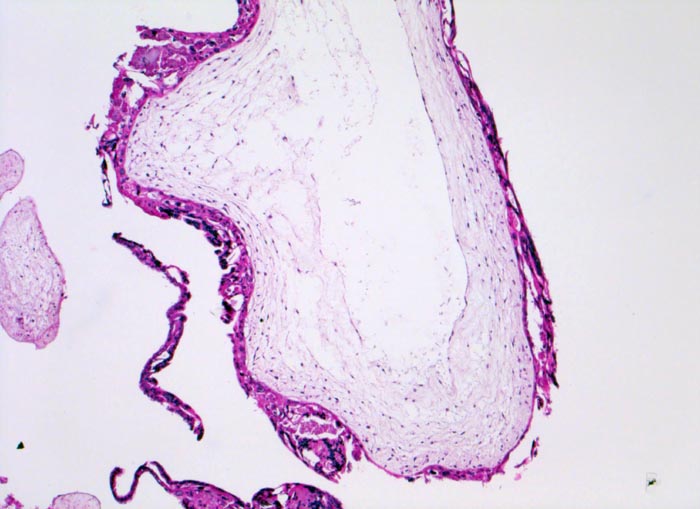

Makroskopisch ist die Plazenta deutlich grösser als erwartet für das Schwangerschaftsalter. Sie ist diffus von bis 2cm grossen Zottenblasen durchsetzt, welche nach Kollaps jedoch der makroskopischen Entdeckung entgehen können. Beim Aufschwemmen in Flüssigkeit entfalten sich die Blasen wieder. Mikroskopisch sind die Zotten aufgrund einer grobblasigen pseudozystischen Hohlraumbildung im Zottenstroma überwiegend grosskalibrig. Im Zottenstroma sind nur ganz vereinzelt Kapillaren nachweisbar. Im Gegensatz zu hydropisch geschwollenen Zotten im Sinne eines Regressionsphänomens zeigen die Zotten bei Blasenmole zusätzlich eine zirkumferentielle Hyperplasie von Synzytio- und Zytotrophoblast mit fakultativer Zellatypie. Bei herdförmiger Mole (> 3725) sind diese Veränderungen nur in einem Teil der Plazentarzotten ausgeprägt.

• Stark vergrösserte und verplumpte Plazentarzotten.

• Hydropisch umgewandeltes Zottenstroma ohne Gefässe mit Ausbildung von pseudozystischen Hohlräumen (Blasen)

• Überschiessend proliferiertes Trophoblastepithel, teils in der gesamten Zirkumferenz der Zotten mit deutlichen Kernatypien. Kein Embryo.